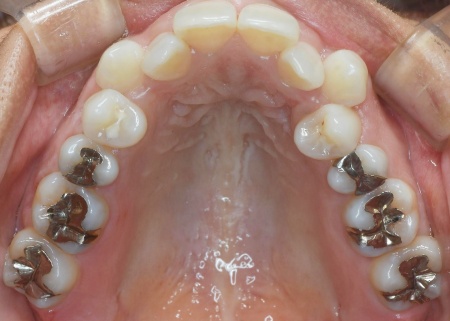

40代女性 デコボコの歯並びと開咬をマウスピース矯正と舌のトレーニングで改善した症例

「奥歯で噛むと上下前歯が触れ合わないので、噛み合わせを治したい。また、歯並びがデコボコしているのも気になる」とご相談いただきました。

拝見したところ、奥歯で噛んだ際に上下の前歯が触れ合わず、隙間ができている状態でした。

これは開咬(かいこう)と呼ばれ、前歯で食べ物を噛み切るのが難しい噛み合わせです。

加えて全体的に歯が重なり合ってデコボコに生えており、歯磨きがしにくく、審美性にも悪影響がでています。

さらに舌で前歯を押す癖もあり、これは開咬の原因だけでなく、矯正治療後に歯並びが戻る原因にもなります。